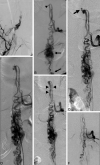

Results: One hundred forty-eight SCAVMs were identified, and 28 (19%) of these were SAMS. Of these 28 patients, 24 had nidus-type AVMs and 4 had fistulas. SAMS were more prevalent in females (71% versus 48%), and also presented earlier than non-SAMS SCAVMs. Intradural hemorrhage (SAH or hematomyelia) was the most common presentation and more common than in non-SAMS lesions. Twenty-six patients underwent embolization of the intradural lesion in 50 sessions. Thirteen patients underwent treatment of intradural aneurysms in 16 sessions. Six patients underwent embolization of extradural lesions in 16 sessions. Twenty-three patients had an average of 94 months of clinical follow-up (3-309 months) after the first treatment, during which 5 patients had hemorrhages. Angiographic follow-up was performed in 20 patients at an average of 85 months (range, 3-309 months), which showed new development or enlargement of an aneurysm in 5 patients. This type of angiographic progression was more common in patients with SAMS.

Conclusions: SAMS most commonly presents with hemorrhage from the SCAVM. Endovascular embolization can be performed safely with good functional outcome, though most patients clinically deteriorate in the long term. Periodic angiographic follow-up with intent to perform preventive target embolization is important to control the disease.